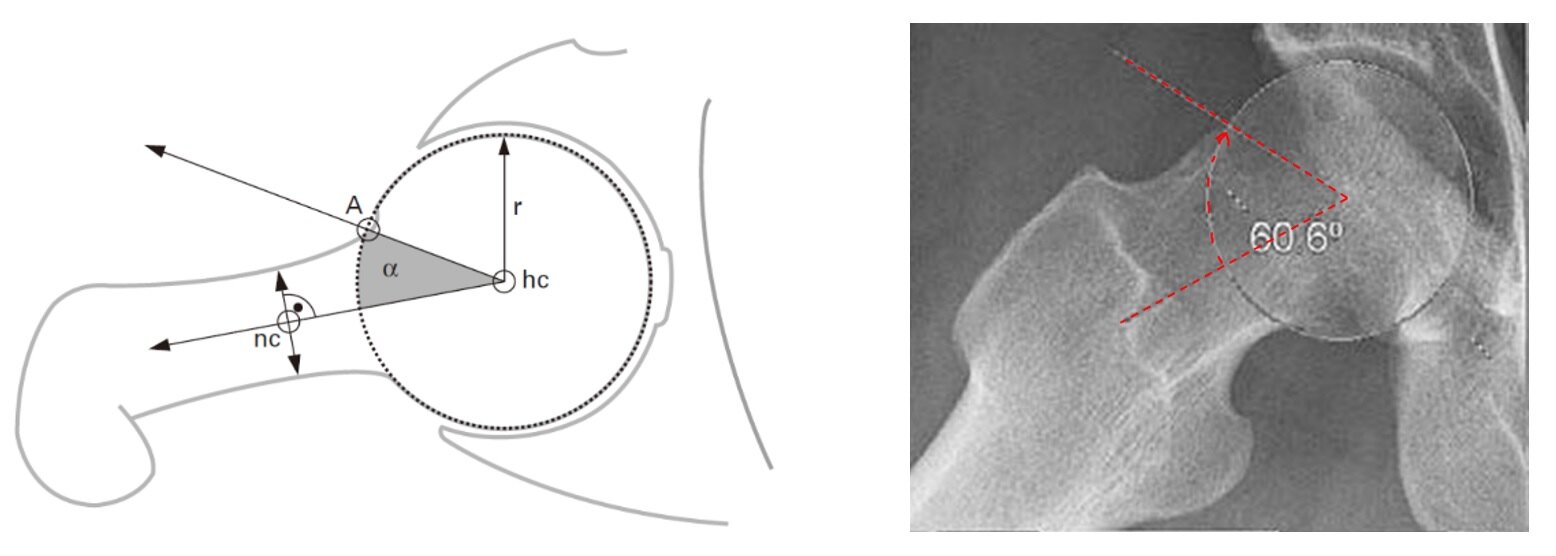

B. α角增大> 50°(45°Dunn位)

图11.患髋45°Dunn位X线片可看到股骨头颈α角增大> 50°。